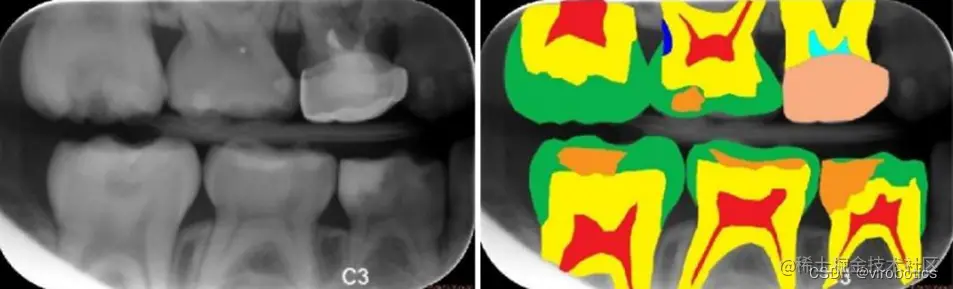

随着人工智能的崛起,将神经网络与医疗诊断结合也成为研究热点,智能医疗研究逐渐成熟。在智能医疗领域,语义分割主要应用于肿瘤图像分割,龋齿诊断等。(下图分别是龋齿诊断,头部CT扫描紧急护理诊断辅助和肺癌诊断辅助) 在这里插入图片描述 在这里插入图片描述